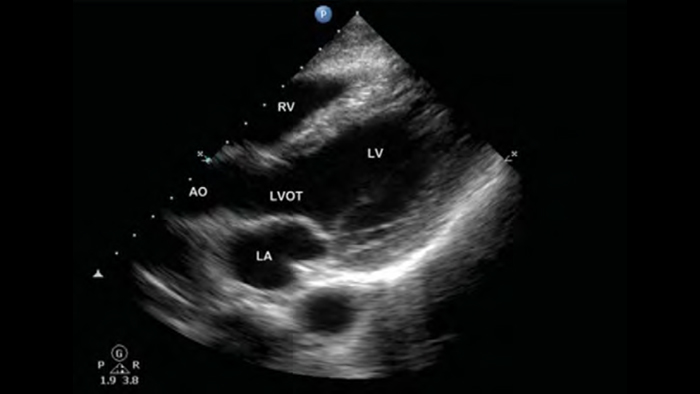

Lumify S4-1 broadband phased array transducer

• 4 to 1 MHz extended operating frequency range

• 2D, color Doppler, M-mode, advanced XRES and multivariate harmonic imaging

• High-resolution imaging for abdominal and cardiac applications: Cardiac, OB/GYN, Lung, Abdomen and FAST imaging preset optimizations